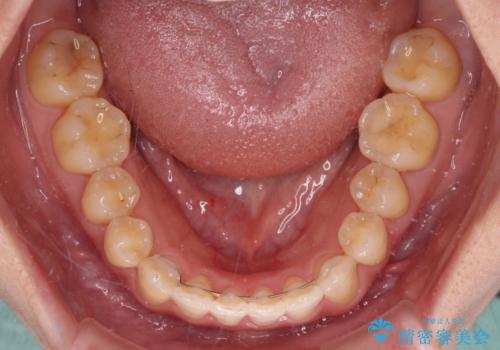

- 上下前歯のデコボコと銀歯のブリッジを気にして来院された患者様です。

装着されているブリッジを切断して矯正治療を行うことや、手間をかけずに早めに治療を終えたいとのことで、目立たないワイヤー装置による矯正治療を行うこととしました。

矯正治療後には切断したブリッジをオールセラミックブリッジに置き換えることとしました。